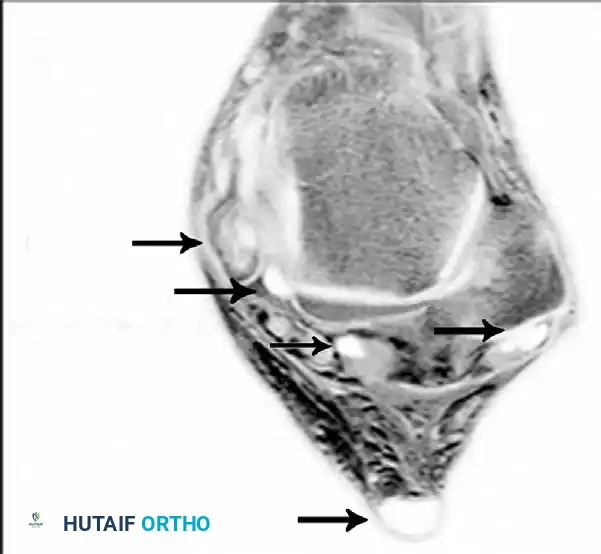

Magnetic Resonance Imaging (MRI)

MRI is highly sensitive for evaluating the integrity of the PTT, spring ligament, and deltoid ligament. T2-weighted and fat-suppressed images excel at demonstrating peritendinous effusions, tendinosis, and interstitial tearing. DeOrio et al. described the "posterior tibial edema sign," where subcutaneous pitting edema along the tendon correlates with MRI evidence of disease in 88% of patients.

Axial MRI slices demonstrating severe tendinosis, fluid within the tendon sheath, and attenuation of the spring ligament complex.